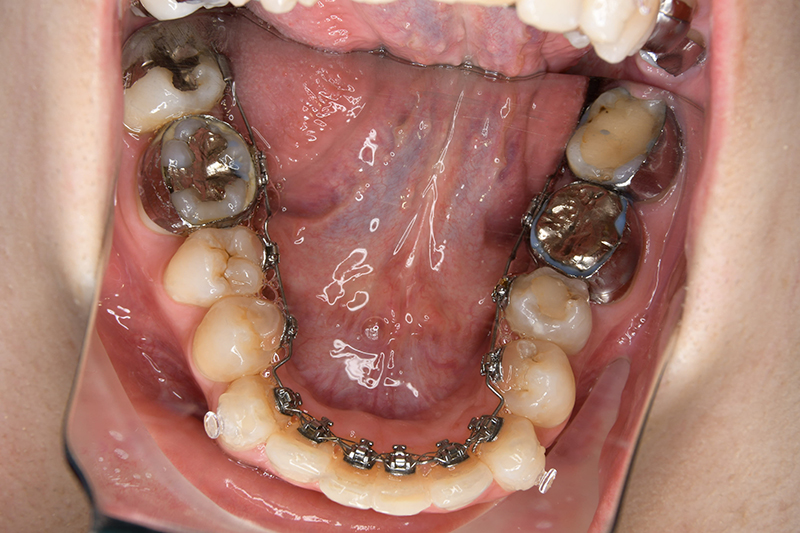

動的治療中のIOP(治療開始後12ヶ月)

動的治療中のIOP

(治療開始後12ヶ月)

IOP